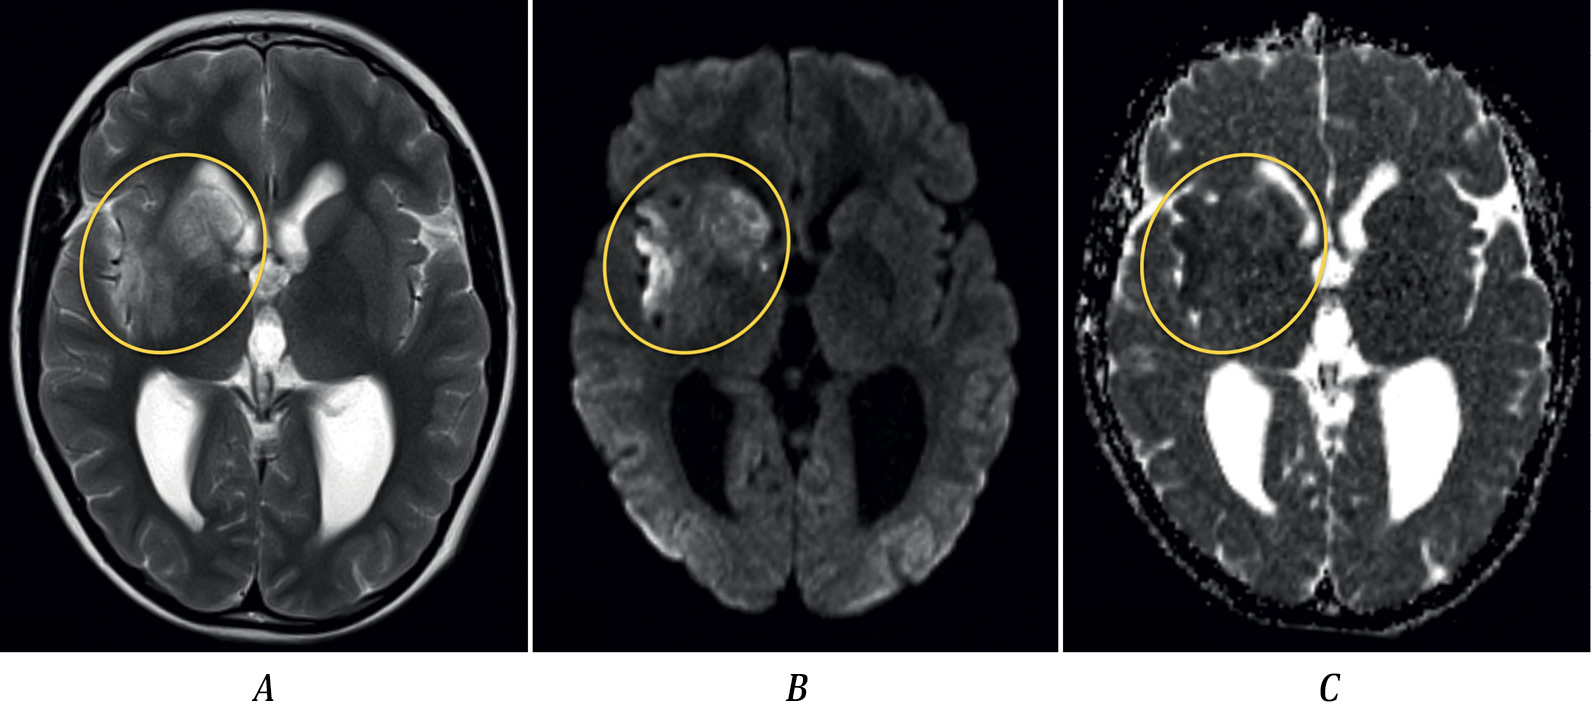

Fig. 1. MRI of patient S. dated 27.01.2017, axial plane.

A — T2-weighted imaging; B — DWI (b-1000); C — ADC map. Heterogeneous areas of increased intensity of MR signal in T2 and DWI (b-1000) sequences, with heterogeneous reduction of MR signal on ADC map (“acute” infarction), are observed in the head of the caudate nucleus, putamen, anterior limb of the internal capsule, and gray/white matter of the insular lobe in the right cerebral hemisphere.

Brain MRI demonstrated an ischemic area in the right MCA territory and hydrocephalus (Fig. 1). MRA performed on January 27, 2017 and analyzed at the Radiology Department of the Russian Center of Neurology and Neurosciences, revealed irregular contours of the M1 segment of the right MCA (Fig. 2, A) and hypoplasia of the A1 segment of the right anterior cerebral artery. No intramural hematoma in the right MCA or pathological vessel wall contrast enhancement was detected. These findings were interpreted as arteriopathy. Echocardiography showed no abnormalities. Routine blood tests, biochemical analysis, and coagulation tests were unremarkable. Antiphospholipid antibodies were negative. Tests for antinuclear factor, anti-DNA, and C-reactive protein were within normal limits. Treatment included heparin followed by acetylsalicylic acid 50 mg and neurotrophic agents. His condition improved, with only mild left arm weakness remaining at discharge. Discharge diagnosis: acute ischemic stroke in the right MCA territory. Arteriopathy.